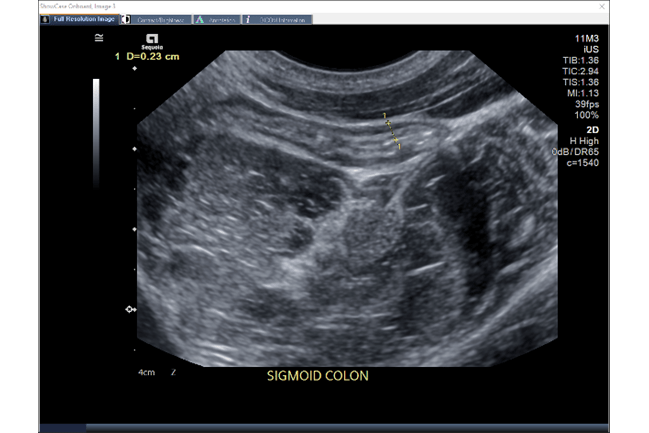

Ultrasound image of the sigmoid colon

IUS is essentially an abdominal ultrasound that provides highly accurate, high-resolution imaging of the intestine and colon. It does not require any of the more intensive bowel preparation needed for invasive procedures like colonoscopies, and it does not have any side effects like those that might occur from radiation.

IUS allows visibility of both the large intestine (colon) and the small intestine (terminal ileum), and disease activity can be assessed using several markers, such as bowel wall thickness, hyperemia (increased blood flow) and disruption of wall layers.

“With IUS, I’m able to see how thick the bowel wall is and if there is an increased blood flow to that area, which would indicate inflammation,” explains Suppa. “I can also see if there is any disruption to the layers of the bowel wall or signs of complications such as strictures.” This allows him to determine how well a patient is responding to a prescribed treatment without waiting for lab results or the need to schedule other procedures or imaging.